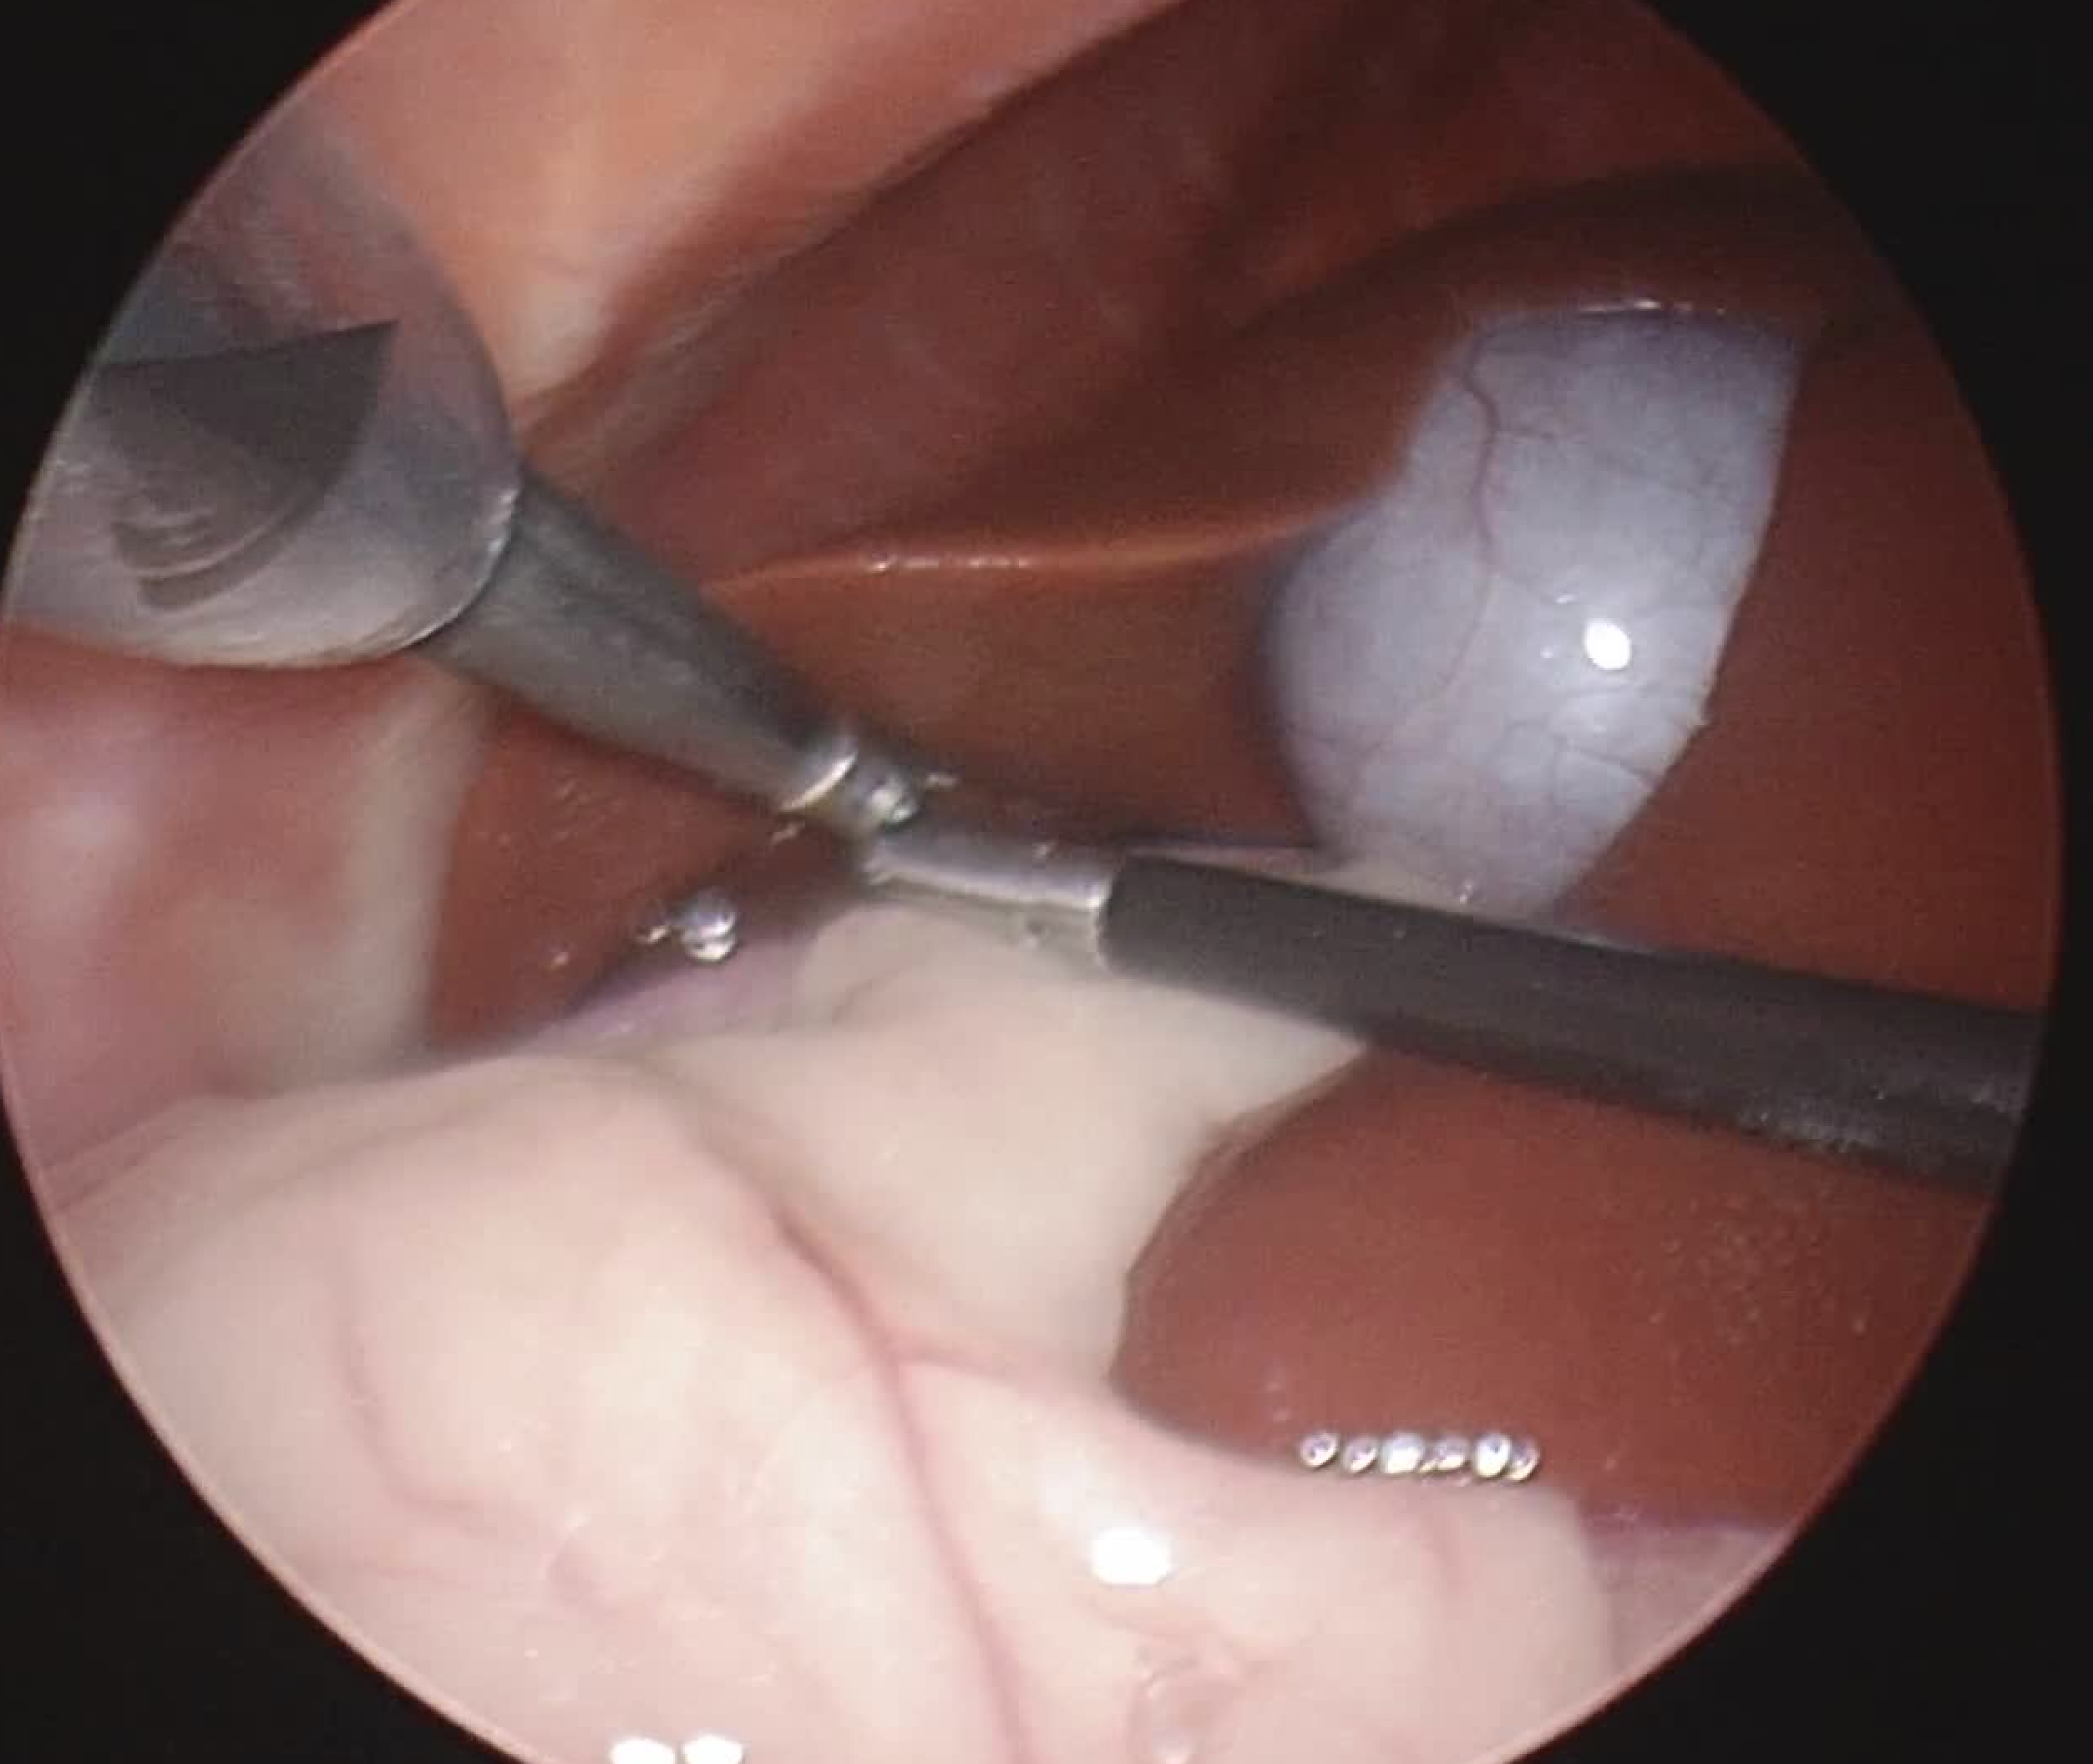

こちらは腹腔鏡を用いた肝生検の様子です。

1枚目の写真は脾臓を示していて、腹腔鏡を用いることで肝臓以外の胆嚢や脾臓など周辺の臓器の確認、出血の程度なども観察しながら手術を行うことが可能です。

腹腔鏡の特徴として、視野を確保するために腹腔内に炭酸ガスを注入して気腹という作業を行います。胸部が圧迫されるため、心臓疾患、肺疾患などの循環や換気に不安がある症例には注意が必要です。